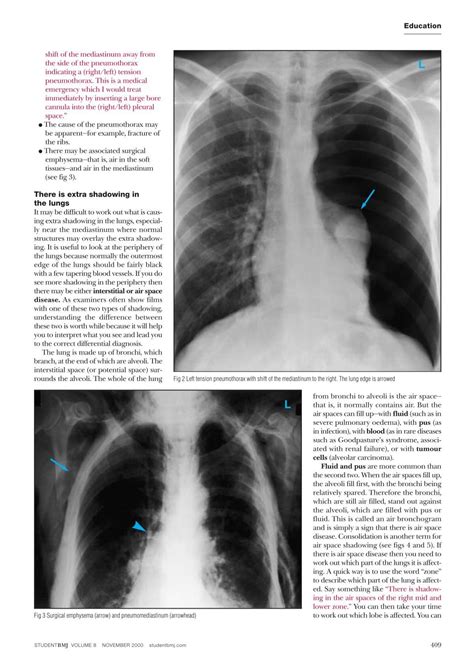

• Pneumothorax: A condition where air leaks into the space between the lung and the chest wall, causing the lung to collapse. This can lead to a shift of the mediastinum towards the unaffected side.

• Tension Pneumothorax: A medical emergency where air accumulates in the pleural space under pressure, pushing the mediastinum and potentially compressing the heart and great vessels.

• Chest X-ray: This is often the first diagnostic test performed. It can show the position of the mediastinum and any abnormalities in the lungs or pleural space.

• Needle Decompression: In cases of tension pneumothorax, a needle may be inserted into the chest to quickly release the trapped air and relieve pressure.

In cases of tension pneumothorax, immediate intervention is crucial. The condition can be life-threatening if not treated promptly. Needle decompression or chest tube insertion is often performed as an emergency procedure to relieve the pressure and stabilize the patient.

• mediastinal shift in pneumothorax